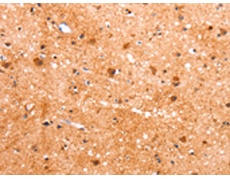

IHC positive control: |

Human brain |

IHC Recommend dilution: |

50-150 |